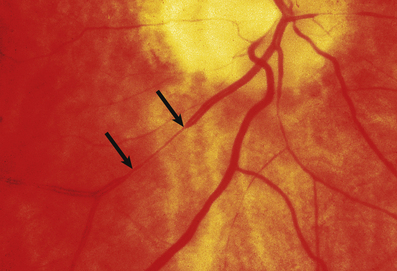

Malignant hypertension is a clinical and pathological syndrome. The characteristic features are a markedly raised diastolic blood pressure, usually over 130–140 mmHg, and progressive renal disease. Renal vascular changes are prominent, and there is usually evidence of acute haemorrhage and papilloedema (Fig. 13.11). Malignant hypertension can occur in previously fit individuals, often black males in their third or fourth decade. However, most cases occur in patients with evidence of previous benign hypertension; this is sometimes termed accelerated hypertension.

image

Fig. 13.11 Hypertensive fundus. Ocular fundus from a patient with hypertension. The outline of the blood vessels is caused by the reflection of light from the column of blood (the light reflex). Because the wall of the arteriole is thickened in hypertension, the lumen of the vessel is narrowed and the light reflex is reduced (between the arrows).

Hypertension accelerates atherosclerosis, but the lesions have the same histological appearances and distribution as in normotensive subjects. However, hypertension also causes thickening of the media of muscular arteries. This is the result of hyperplasia of smooth muscle cells and collagen deposition close to the internal elastic laminae. In contrast to atherosclerosis, which affects larger arteries, it is the smaller arteries and arterioles that are especially affected in hypertension (Fig. 13.11).